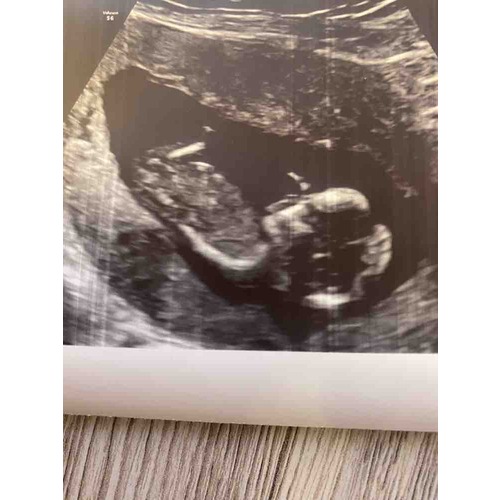

Is het op deze foto beter te zien? Meer foto's heb ik helaas niet🤔

Iemand die hier iets op kan zien? 13+3 weken😄

Geen nub. Maar gok toch echt jongen. Steekt te ver uit voor een meisje lijkt mij

Een jongen.